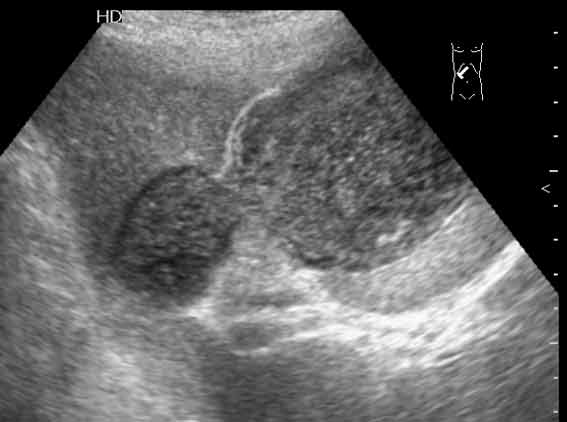

Острый холецистит, эмпиема и перфорация желчного пузыря.

Tags: Acute cholecystitis, empyema and perforation of the gallbladder.